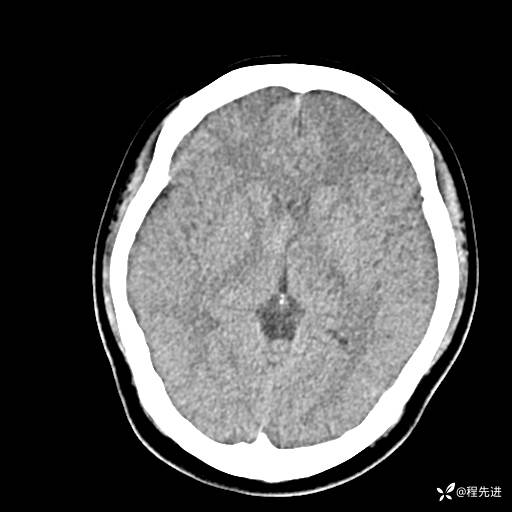

CT平扫: